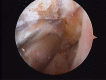

Material and methods: Of the 22 patients who were treated; 18 males and 4 females, and aged from 17-42 years (mean 28 years). All patients presented a history of more than three ankle sprains in the last two years and presented positive anterior drawer and talar tilt test of the ankle in the physical examination. We perform an anterior arthroscopy of the ankle in order to treat asociated disease and then we performed "All inside¨ lateral ligament repair through two portals (anteromedial and anterolateral) using an anchor knotless suture.

Conclusion: Several surgical procedures have been described during the last years in order to treat chronic ankle instability. ¨All inside¨ lateral ligament reconstruction presents lower local morbidity than open procedures with few complications. Moreover, it is a reproductible technique, with high clinical success rate, few complications and relatively quick return to sports activities. A high knowledge of the anatomic landmarks should be essential to avoid unwated injuries.